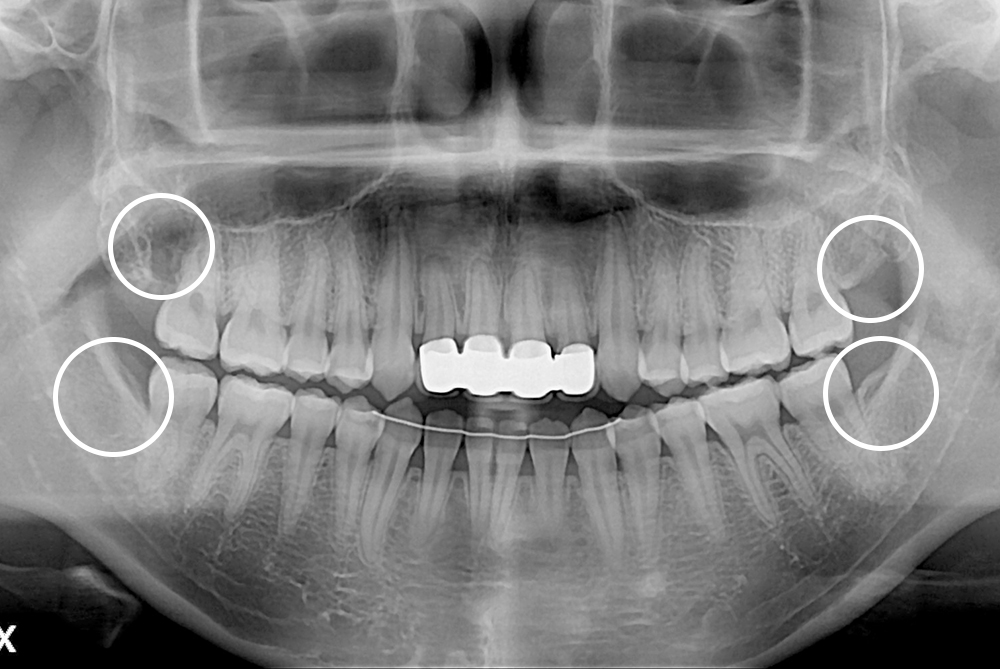

[사랑니] 매복 사랑니 발치

치료전 : 2017-06-12